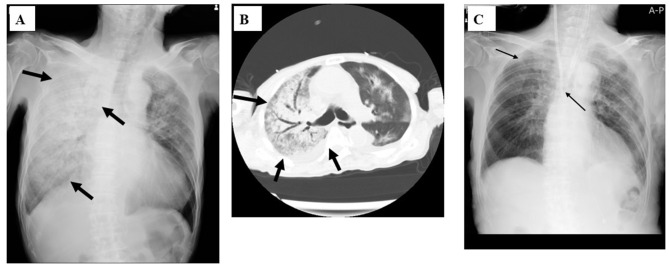

Case series: Four adult cases of M. pneumoniae pneumonia that required admission to the hospital in the 2024-2025 season are presented. Case 1: a 17-year-old male without a specific medical history who was admitted with pneumonia with a severe dry cough. Mycoplasma. pneumoniae genes were detected by multiplex PCR from his sputum. The patient's condition improved with minocycline and corticosteroids for 5 days. Case 2: a 88-year-old man with acute kidney injury who was admitted with severe respiratory failure. Mycoplasma antigen was detected in his pharyngeal swab. He received lascufloxacin drip infusion with corticosteroids for 10 days, and soon improved. Case 3: a 38-year-old woman with maxillary carcinoma and a history of aplastic anemia who was admitted with a severe cough. Mycoplasma antigen was detected in her pharyngeal swab. She received minocycline and corticosteroid drip infusion for 1 week, and finally improved. Case 4: a 74-year-old man with multiple systemic atrophies who was admitted with a severe cough and dyspnea. Mycoplasma antigen was detected from his pharyngeal swab and methicillin-susceptible Staphylococcus aureus (MSSA) was isolated from his sputum. The patient was diagnosed with co-infection with mycoplasma and MSSA. He was treated with sulbactam/ampicillin drip infusion and oral administration of minocycline for 2 weeks, and improved.

Conclusion: All hospitalized adult patients with mycoplasma pneumonia were treated with antibiotics, such as minocycline and fluoroquinolone, along with corticosteroid co-administration, and all of them ultimately improved, although the chest X-ray findings varied. Antibiotics other than macrolides and corticosteroids may be an effective regimen for the treatment of severe mycoplasma pneumonia with potential macrolide resistance.